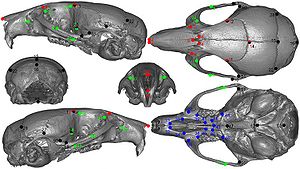

Publication: Front Zool. 2015 Dec 1;12:33. PMID: 26628903 | PDF Authors: Young R, Maga AM. Institution: Center for Developmental Biology and Regenerative Medicine, Seattle Children's Research Institute, Seattle, WA, USA. Background/Purpose: Here we present an application of advanced registration and atlas building framework DRAMMS to the automated annotation of mouse mandibles through a series of tests using single and multi-atlas segmentation paradigms and compare the outcomes to the current gold standard, manual annotation. Results: Our results showed multi-atlas annotation procedure yields landmark precisions within the human observer error range. The mean shape estimates from gold standard and multi-atlas annotation procedure were statistically indistinguishable for both Euclidean Distance Matrix Analysis (mean form matrix) and Generalized Procrustes Analysis (Goodall F-test). Further research needs to be done to validate the consistency of variance-covariance matrix estimates from both methods with larger sample sizes. Conclusion: Multi-atlas annotation procedure shows promise as a framework to facilitate truly high-throughput phenomic analyses by channeling investigators efforts to annotate only a small portion of their datasets. Funding:

|

Visualization of the distances between the atlas surface that was landmarked (p90) and four other surfaces constructed. a 50 % Probability surface (p50); b 70 % Probability surface (p70); c Surface thresholded at grayscale value of 35. d Surface thresholded at grayscale value of 55. RMS: Root mean square error. Segmented left hemi-mandibles were imported into 3D Slicer and visualized using a fixed rendering and threshold setting. |